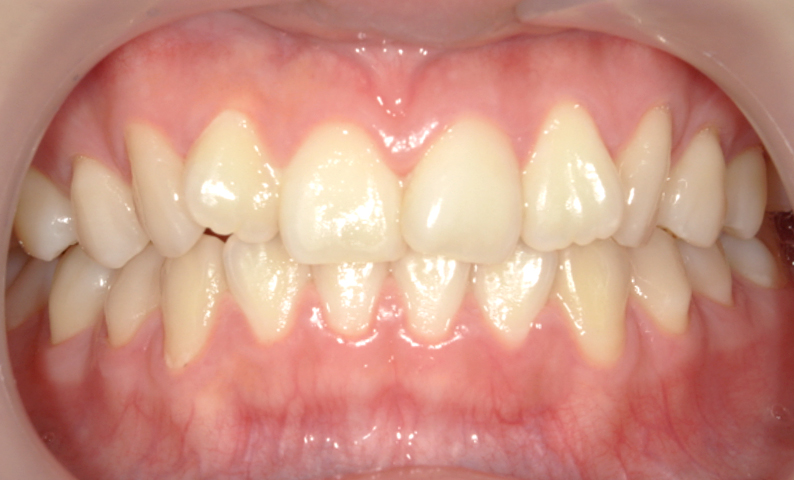

症例_004 上下顎の部分矯正

治療期間:8ヶ月金額:54万円+税女性前歯のガタガタ捻転歯

| Before | After |

|---|---|

|